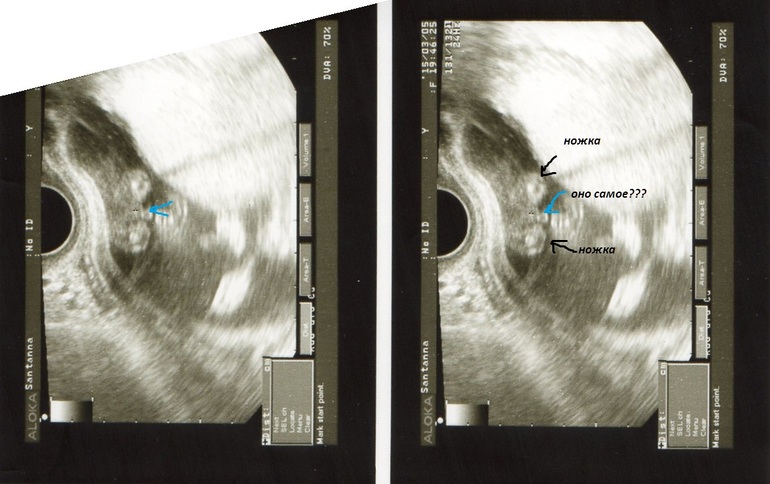

Девчули, кто делал узи на 16-17 неделях и узнал пол - гляньте, если не сложно поделитесь своими фотками. Я просто до сих пор не могу поверить, что наш Марк превратился в девочку!!! Может ошибка, кто помнит фото "бубенчиков"? Девочкины мамы - что скажите??? На фото две согнутые ноги и между ними стрелка указывает на половые органы, подписано "девочка".

Да, как будто сидит на экране раздвинув ножки. Стрелка указывает на половые органы.